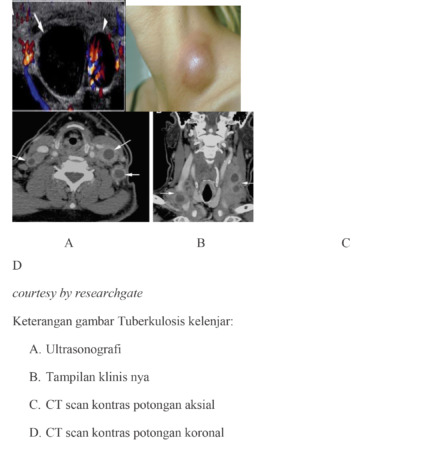

Pada USG leher, kelenjar yang meradang cenderung membesar, membulat, dan hipoekoik atau kehitaman dibandingkan dengan otot-otot yang berdekatan, tanda panah (gambar A). Secara klinis TBC kelenjar tampak sebagai benjolan kemerahan, antar lain di leher (gambar B). Pada CT scan leher, bermanifestasi sebagai pembesaran kelenjar getah bening hypodens atau kehitaman, bentuk oval, disepanjang otot sternokleidomastoid atau di daerah supraklavikula, tanda panah (gambar C).   Kelenjar getah bening supuratif menunjukkan fokus  keradangan di sentral dengan kapsul  tebal, tanda panah (gambar C dan D).